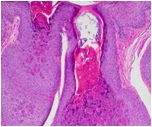

The laboratory provides comprehensive diagnostic services on skin specimens, including histologic interpretation, histochemistry, immunohistochemistry, direct immunofluorescence study, immunophenotyping study, and molecular diagnostics. We provide prompt service with a turnaround time of 24 hours.

biopsy pic 1 biopsy pic 2 biopsy pic 3 biopsy pic 4